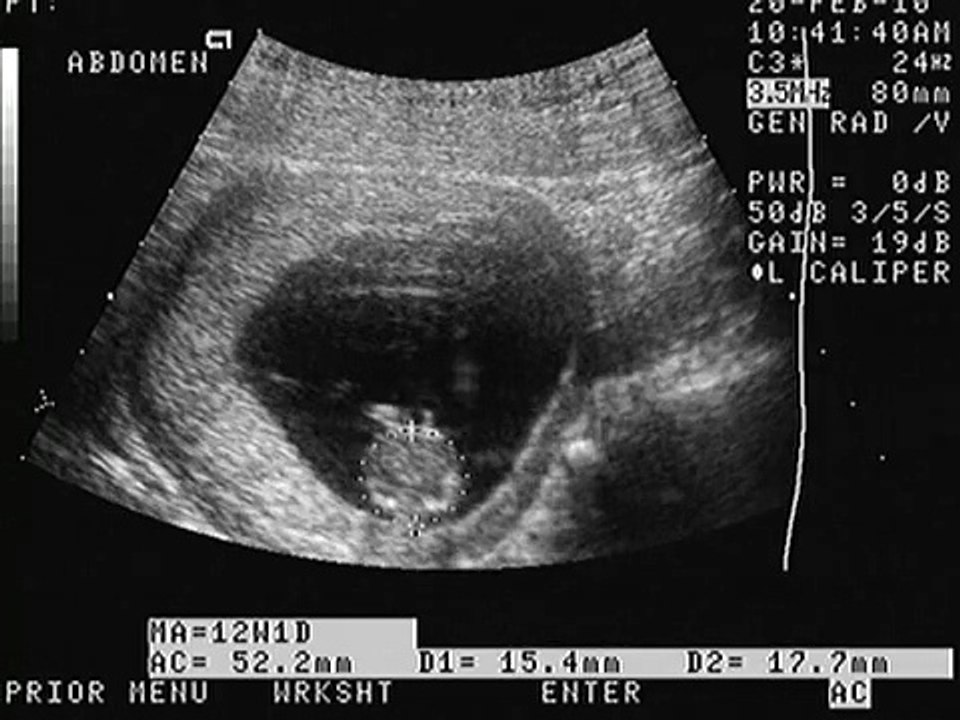

ULTRASONIDO OBSTETRICO DE IMELDA... EMBARAZO DE 12 SEMANAS DE GESTACION... 9:03

ULTRASONIDO OBSTETRICO DE IMELDA... EMBARAZO DE 12 SEMA...

Jacinda Boyce 3 views